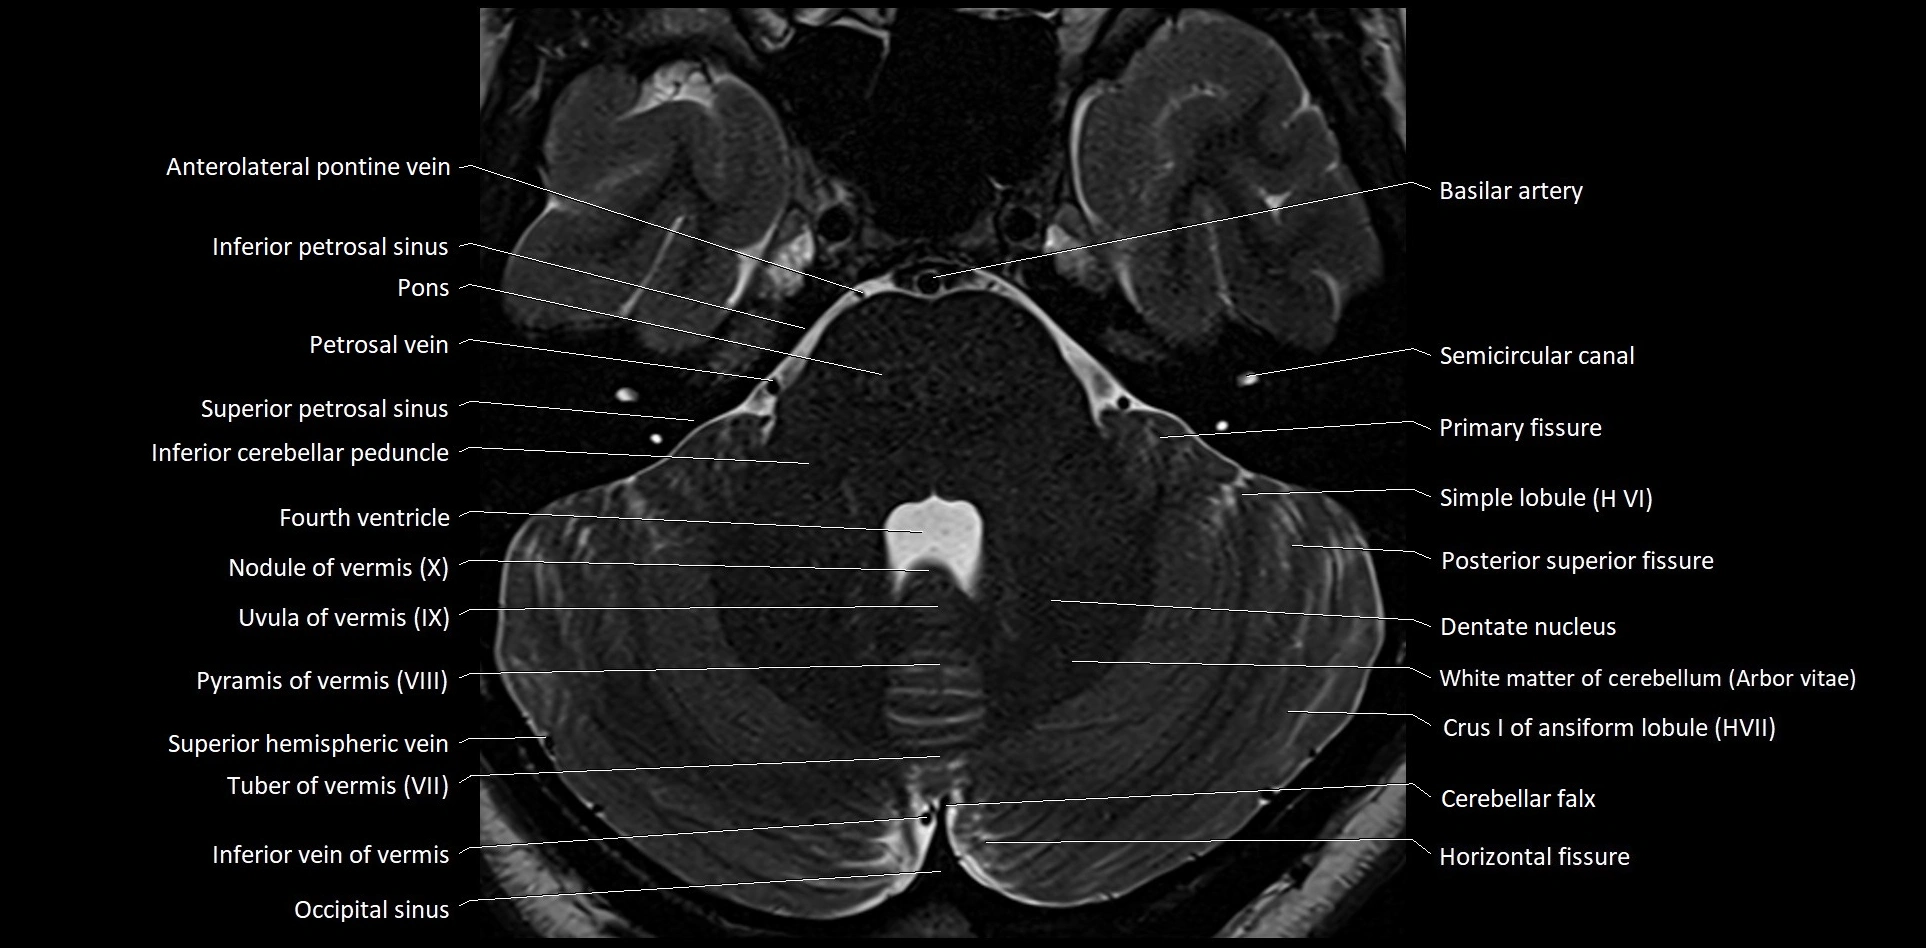

- Anterolateral pontine vein

- Arbor Vitae (Cerebellar White Matter)

- Cerebellar falx

- Dentate nucleus

- Horizontal fissure (cerebellum)

- Inferior cerebellar peduncle

- Inferior petrosal sinus

- Inferior vein of vermis

- Nodule of vermis

- Nodule of vermis (X)

- Occipital sinus

- Petrosal vein

- Posterior superior fissure

- Primary fissure

- Pyramid of vermis (VIII)

- Pyramis of vermis

- Semicircular Canals

- Simple lobule

- Simple lobule (HVI) of cerebellum

- Superior petrosal sinus

- Uvula of vermis (IX)

- White matter of cerebellum (Arbor vitae)